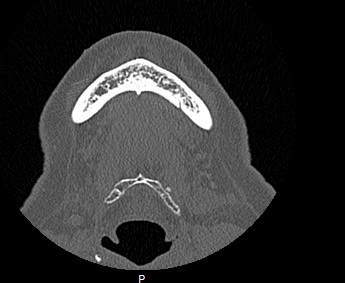

Мультиспиральная компьютерная томография челюстно-лицевой области относится к лучевым методам исследования и включает в себя сканирование верхней и нижней челюстей, зубов, височно-нижнечелюстных суставов, мягкотканных структур ротовой полости. Преимуществами КТ является быстрота, безболезненность и неинвазивность (то есть исследование не требует вмешательства в организм).

В результате сканирования получается серия изображений, которые отображают состояние челюстно-лицевой зоны, особенности анатомического строения и позволяют выявить воспалительные изменения, травматические повреждения, опухолевые образования, аномалии развития. Проявления артроза височно-нижнечелюстных суставов могут создавать неприятные ощущения при жевании. Также зачастую воспалительные изменения придаточных пазух носа связаны с пролабированием зубов верхней челюсти в область альвеолярных бухт верхнечелюстных синусов.

В наших медицинских центрах обследование челюстно-лицевой зоны проводится на современных мультиспиральных компьютерных томографах экспертного класса TOSHIBA AQUILION. 64- и 128-срезовый компьютерные томографы послойно сканируют исследуемую область с шагом от 0,5 мм, получая детальные изображения высокого уровня четкости и контрастности.

С помощью цифровой обработки данных проводится объемная реконструкция и построение 3D-изображений челюстно-лицевой области, что дает возможность визуализировать пространственное соотношение анатомических структур и повышает точность диагностики. При этом возможности аппаратов обеспечивают пониженный уровень дозы облучения для организма человека.